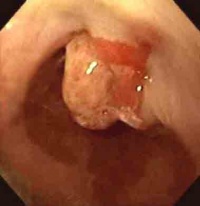

食管癌[编辑 | 编辑源代码]

食管癌发生于世界各国,其高发区有显著的地理性差异。2000多年以前中国豫西一带已有“噎膈”的记载。多数学者认为食管癌是由环境中的致癌因素引起。已提出的致癌因素包括亚硝胺类化合物和霉菌毒素。食物中缺乏某些微量元素、铁、锌、氟可能起间接促作用。吸烟、饮酒在某些国家可能为主要病因,在中国不占重要地位。某些食品(如酸菜含有霉菌)和饮食习惯(如喜过热食物等)可能与发病有关。营养不良、摄入蛋白质不足、维生素A、B、C缺乏可能是发病的一种条件,总之食管癌可能是多种原因共同作用的结果,而以致癌物为主要因素。已知的致癌物虽能诱发动物食管癌,但没有一种为大家所公认。 食管癌的确切病因不明。显然,环境和某些致癌物质是重要的致病因素。

食管黏膜